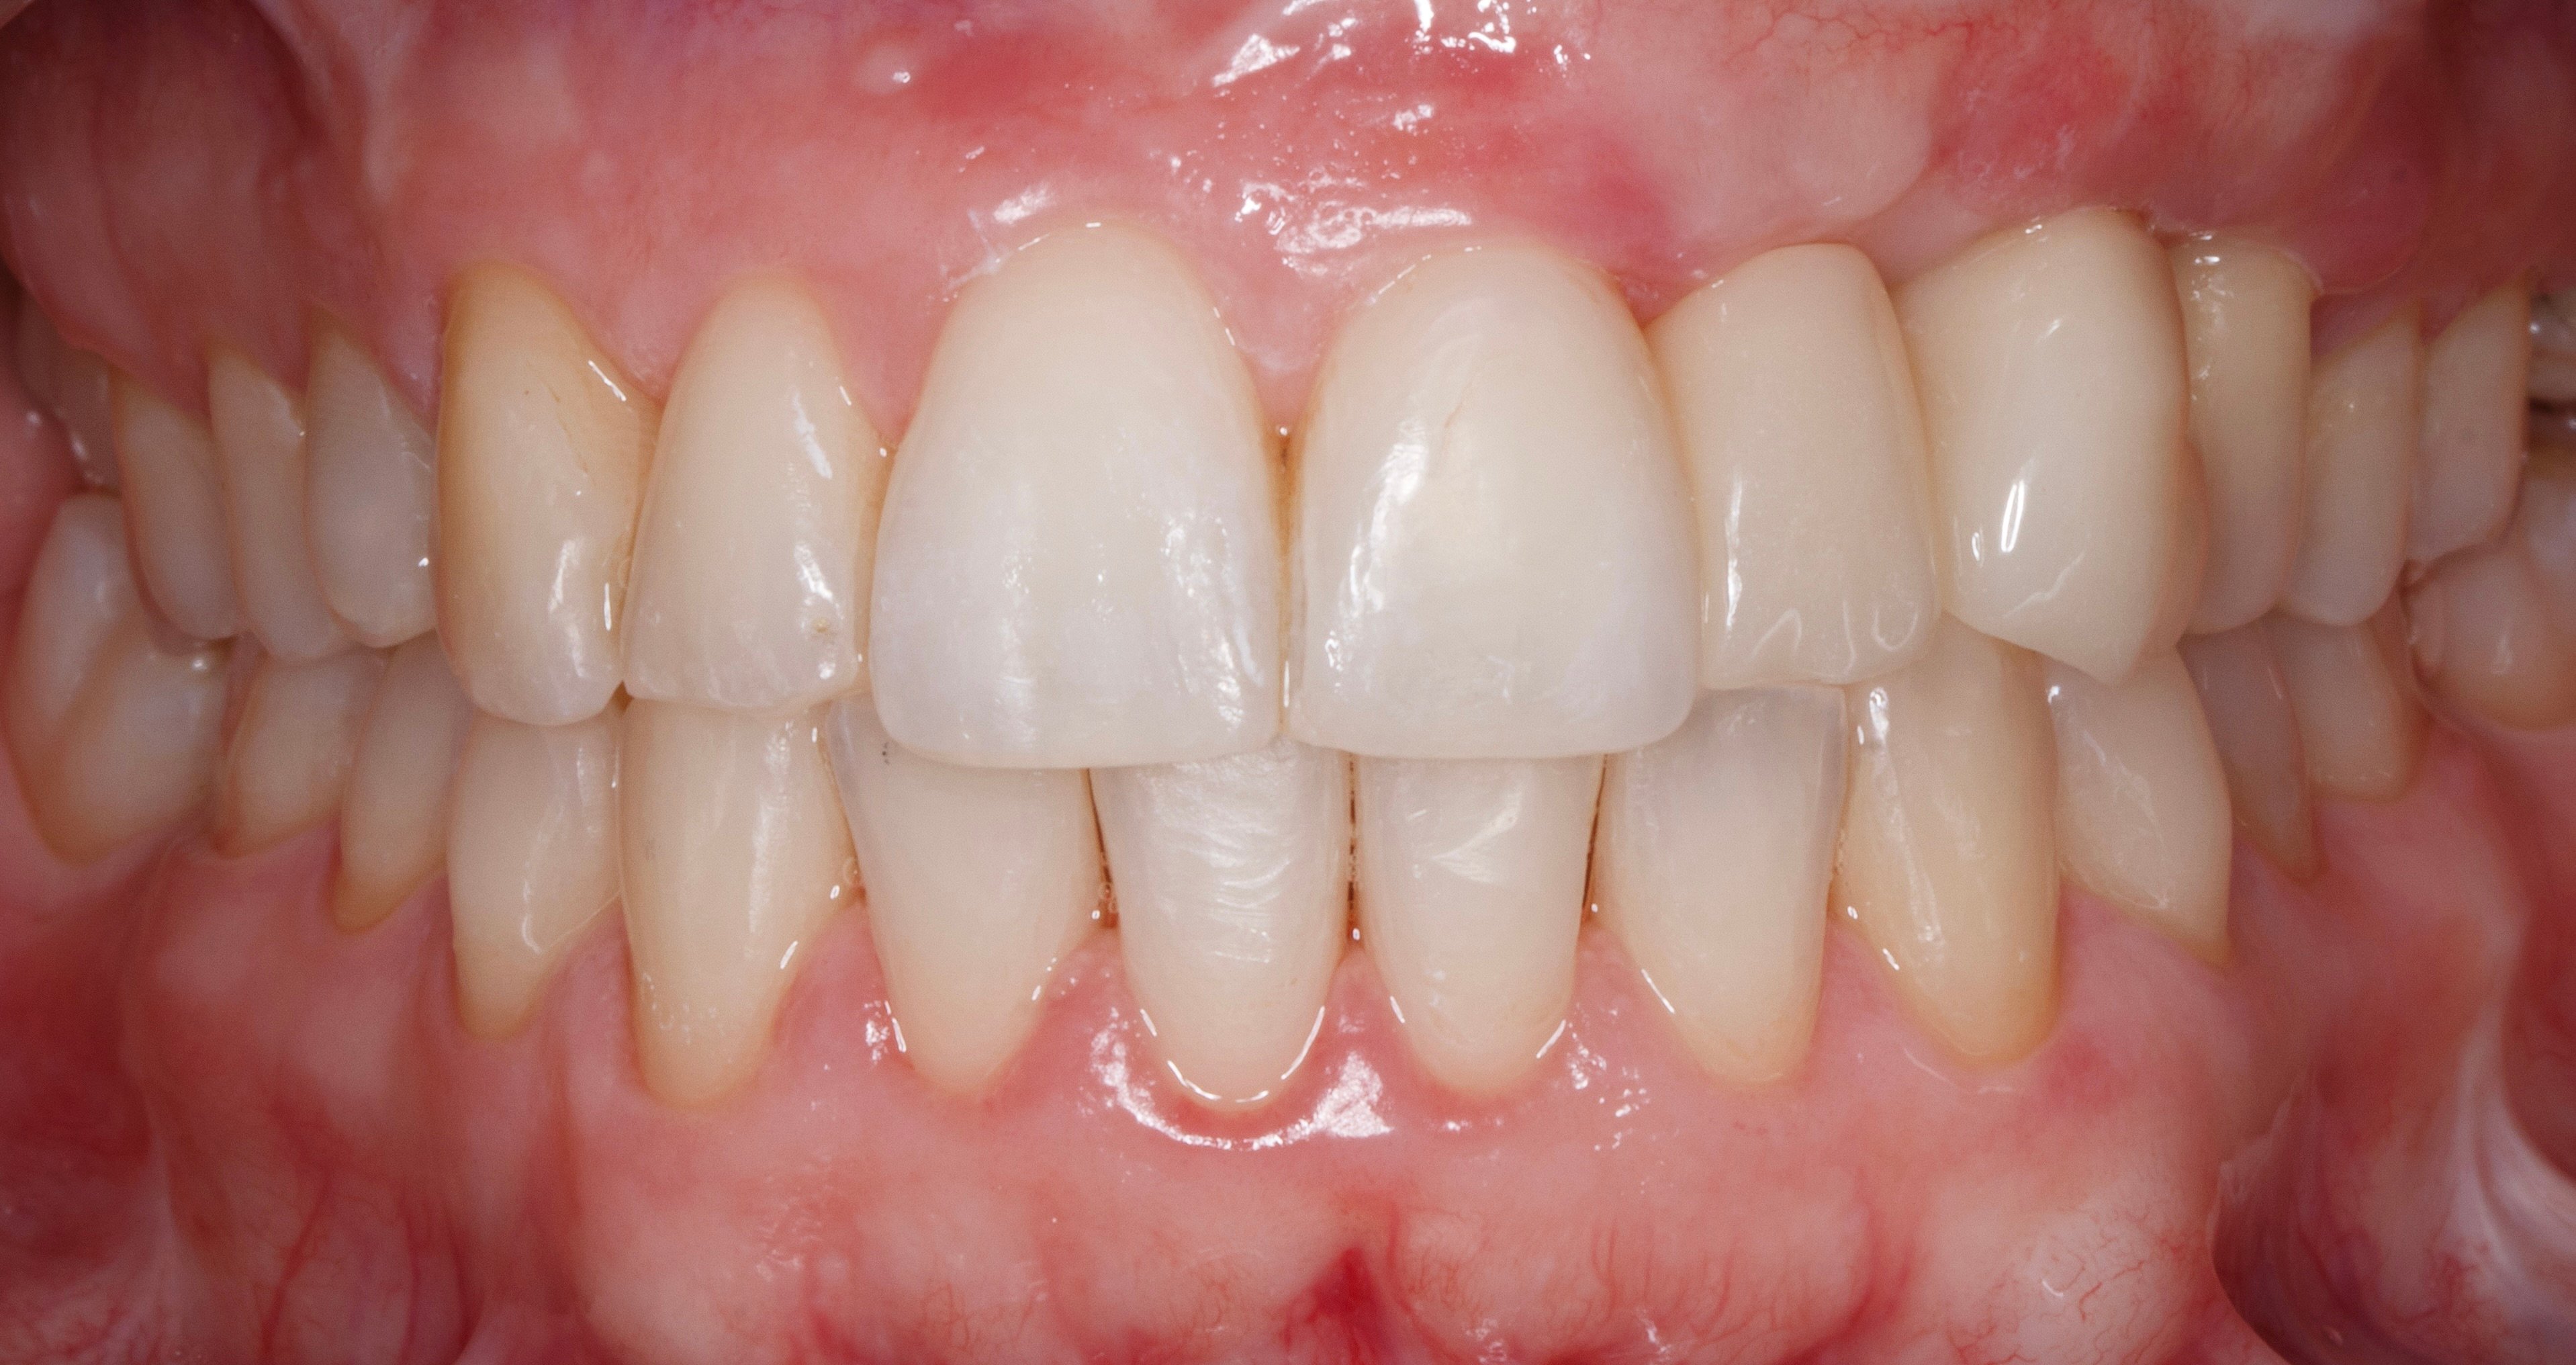

- 2 years later: Final prosthesis.

- 4 years later: Clinical and Radiographic Evolution of the Aesthetic Zone.

3D guided bone regeneration using an e-PTFE, Ti-reinforced NeoGen® membrane and 100% autogenous bone is a fully predictable treatment for the severe hard and soft tissue atrophy on the Aesthetic Zone. This statement is supported not only by panoramic and periapical x-rays, but also by CBCT sectional cuts where we can see the complete stability of the regenerated bone.